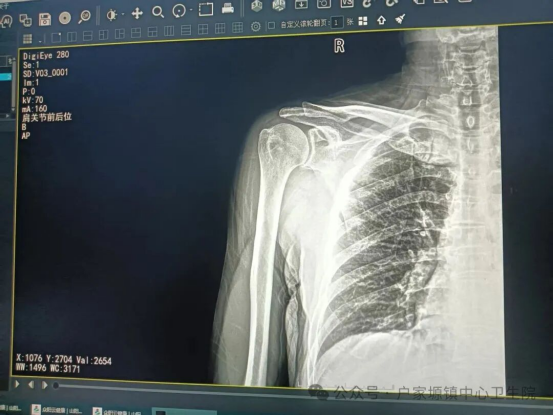

患者就诊时,肩关节明显畸形、疼痛剧烈,活动完全受限,情绪十分焦虑。接诊医生立即对患者进行详细查体及影像学检查,明确诊断为新鲜肩关节脱位,排除骨折、神经血管损伤等禁忌证后,迅速通知我院外科团队,制定了安全高效的手法复位方案。

复位过程中,团队分工协作,一边耐心安抚患者情绪、分散其注意力,一边严格按照规范操作流程,凭借丰富的临床经验和娴熟的操作技巧,精准发力、巧妙复位。随着“咔哒”一声轻响,脱位的肩关节顺利归位。复位后,柯先生的疼痛感瞬间消失,胳膊也能正常活动,他激动地说道:“太谢谢你们了!本来以为得去县城医院,没想到咱镇卫生院的医生技术这么棒,又快又专业,真是太厉害了。